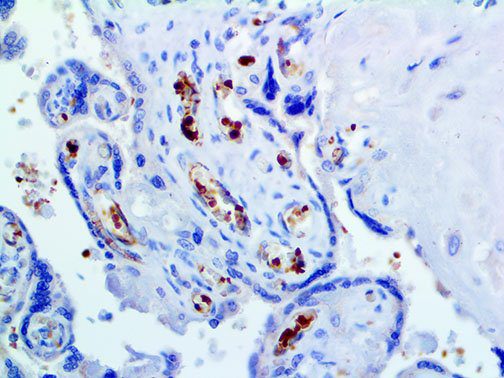

It is the ICU physician who is most likely to witness one of the deadliest manifestations of the abnormal immunological response, the cytokine storm syndrome (CSS). This response is also referred to by some as the cytokine release syndrome (CRS). CSS is characterized by continuous activation and expansion of macrophage and lymphocyte populations, which secrete large amounts of cytokines, causing the cytokine storm. This massive cytokine release is akin to hemophagocytic lymphohistiocytosis (HLH) disease, a syndrome characterized by initial unchecked and persistent activation of cytotoxic T lymphocytes and NK cells.

Clinical and laboratory manifestations of HLH include fever, enlarged liver and/or spleen, neurologic dysfunction, coagulopathy, liver dysfunction, cytopenias (i.e., low levels of erythrocytes, leukocytes, and/or platelets), hypertriglyceridemia, hyperferritinemia, hemophagocytosis, and eventually diminished NK cell activity as the immune system becomes progressively paralyzed. HLH can be familial (primary HLH) or secondary to another disease process (sHLH), such as rheumatic disease, in which it is referred to as macrophage activation syndrome (MAS, characterized by elevated ferritin).